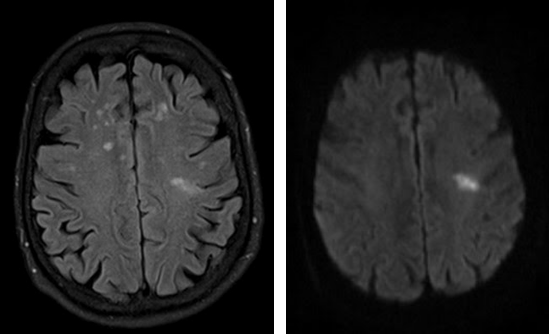

Подозрения на инсульт. Симптомы, которые могут указывать на ишемический процесс или кровоизлияние. Неврологический дефицит, интенсивная головная боль. Также тошнота, неукротимая рвота, параличи, парезы. МРТ показывает очаги патологии, области поражения сосудистых структур.

Рисунки 2,3. МРТ головного мозга. ОНМК по ишемическому типу в левой лобной доле. Очаговые изменения вещества головного мозга сосудистого характера.

Инсульт. Острое нарушение мозгового кровотока. С помощью томографии удается выявить очаг поражения, определить степень тяжести расстройства и разработать тактику лечения. Врачи действуют быстро